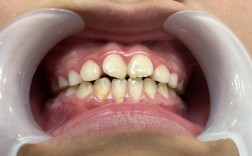

这是最核心的因素,简单的牙齿问题,如轻度拥挤、少量牙缝不齐,通常移动距离短、难度低,矫正时间可能较短;而复杂问题,如严重的牙齿拥挤、深覆合(上牙完全覆盖下牙)、深覆盖(龅牙)、骨性错颌(上下颌骨发育不协调)等,不仅需要牙齿移动,可能还需要配合颌骨调整或牙齿代偿性移动,时间自然会延长,单纯排齐前牙可能需要6-12个月,而伴有骨性问题的“地包天”,可能需要2-3年甚至更久的综合治疗。